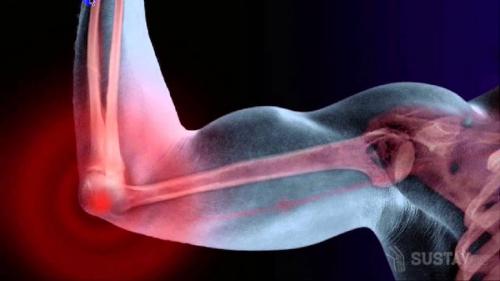

Перелом локтевого сустава. Виды переломов локтевой кости

По месту расположения области перелома обычно выделяют:

- Перелом локтевого отростка и верхней трети кости, находящейся в непосредственной близости к суставу – опасная травма, как правило, сопровождающаяся повреждением сустава и связок. Происходит, чаще всего, вследствие сильного дробящего удара по локтю либо неудачного падения на согнутый локоть с высоты своего тела и более. Такой перелом может самым серьезным образом сказаться на подвижности локтевого сустава в течение всей жизни, особенно в случае несвоевременного или неправильного лечения.

Перелом локтевого сустава рентген. Переломы локтевого отростка

Анатомия перелома локтевого отростка

Перелом локтевого отростка происходит в основном при падении на локоть с высоты собственного роста. Существуют случаи, когда данному перелому характерен вариант со смещением. Чаще всего он происходит на уровне верхушки отростка, но иногда несет за собой внесуставное повреждение. Именно к этому участку крепится сухожилие трехглавой мышцы плеча (трицепса), которое “тянет” отломанные элементы проксимально (в сторону плеча), тем самым создавая диастаз промежуток между отломками, что является серьезным препятствием для сращения перелома.